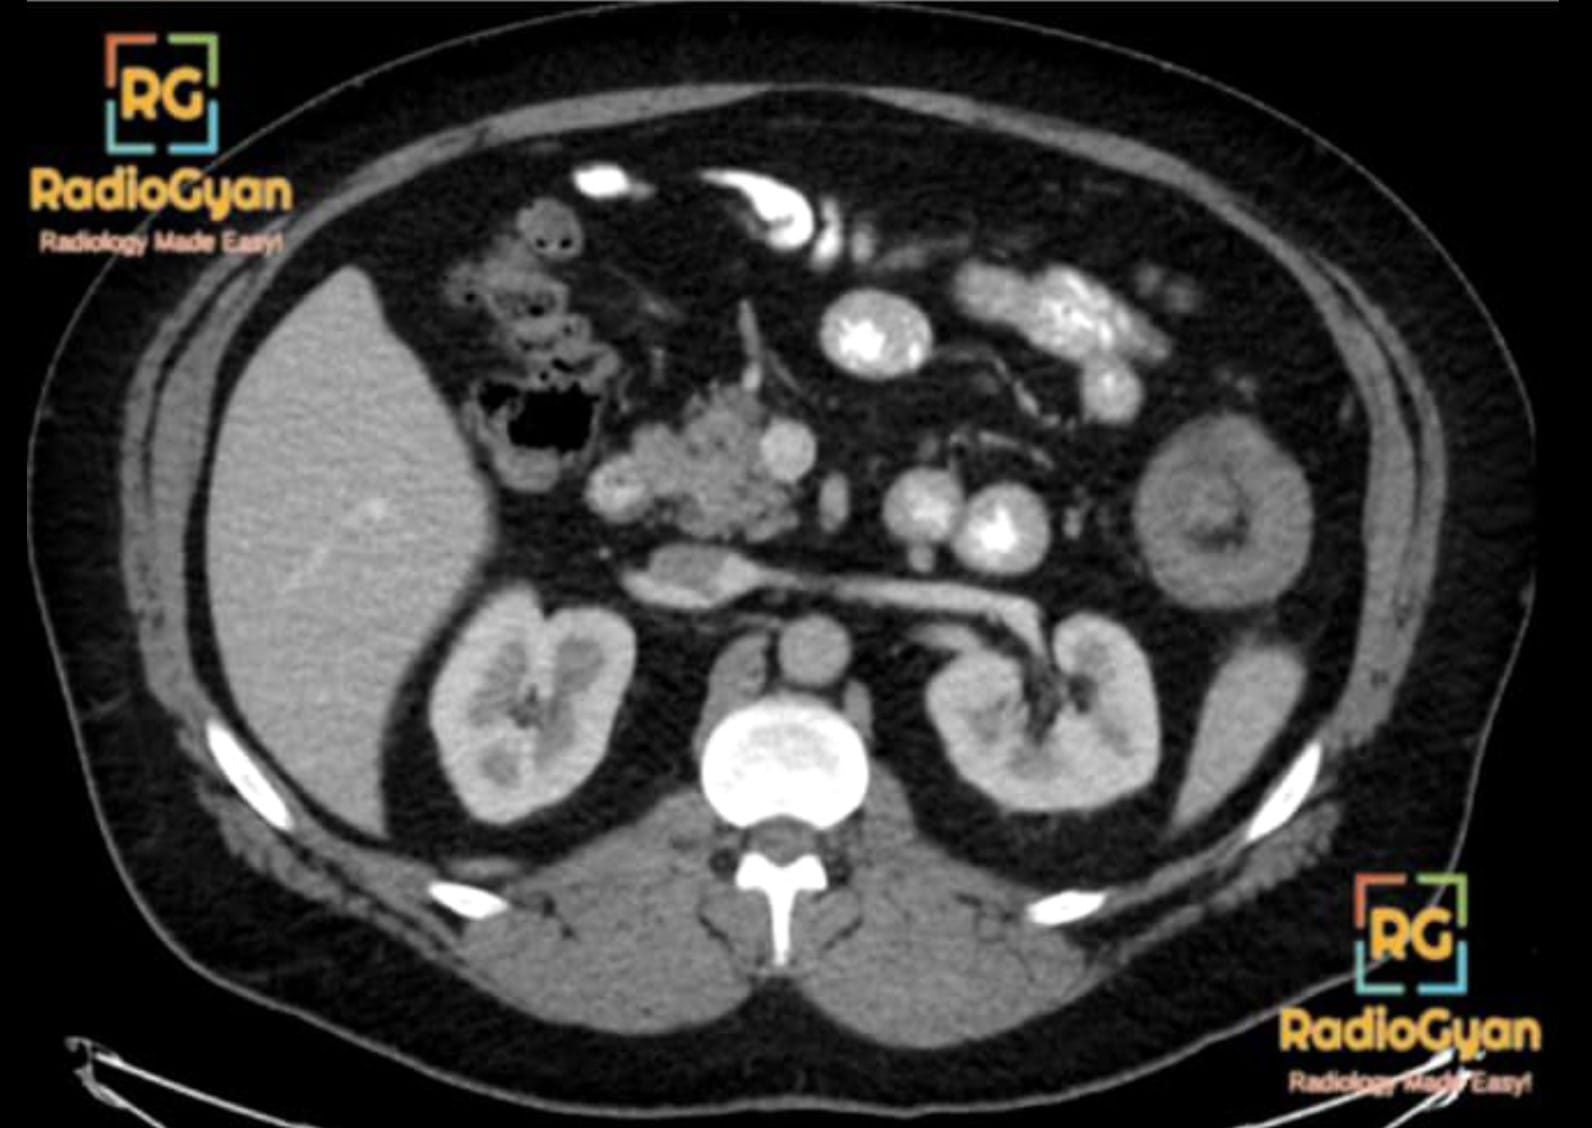

Inframesocolic spaces on Coronal CT

Right and Left Inframesocolic Spaces

The ascending and descending colon separate the right and left inframesocolic compartments (RMC and LMC respectively) from the paracolic gutters.

The right inframesocolic space is smaller than the left and is limited inferiorly by the attachment of the small bowel mesentery to the cecum. It is for this reason that collections in this space generally do not extend into the pelvis. The left inframesocolic space is larger and has free communication with the pelvis.

Inframesocolic spaces on Axial and Coronal CT